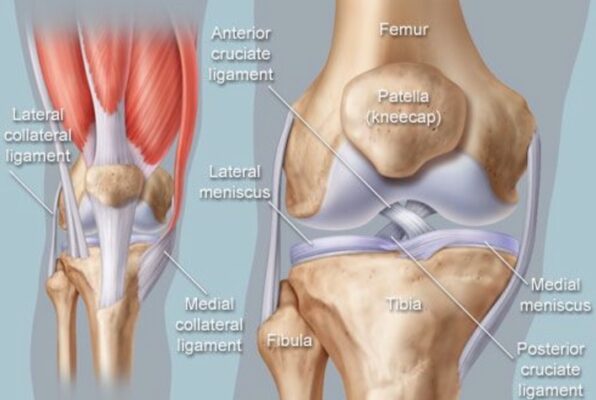

Các dây chằng:

Khớp chày đùi có bốn dây chằng chính:

- Dây chằng bên trong (MCL, medial collateral ligament) là dây chằng hình tam giác dẹt bao phủ một phần rộng mặt trong khớp. MCL nâng đỡ chống lại lực từ bên ngoài (valgus) và một phần kháng lại xoay trong và xoay ngoài. MCL cung cấp 78% tổng lực kháng valgus ở tư thế gối gấp 25°.

- Dây chằng bên ngoài (LCL, lateral collateral ligament) mỏng hơn MCL, chống lại lực từ bên trong (varus), căng khi duỗi và giảm chiều dài khoảng 25% khi gấp tối đa. LCL cung cấp 69% lực kháng varus ở tư thế gối gấp 25°.

- Dây chằng chéo trước (ACL, anterior cruciate ligament) tạo cản chính (85%) vận động ra trước của xương chày so với xương đùi. ACL dài hơn PCL 40%. Các phần khác nhau của ACL căng ở tư thế gối khác nhau nhưng nói chung ACL được xem là căng ở tư thế gối duỗi.

- Dây chằng chéo sau (PCL, posterior cruciate ligament) tạo cản chính (95%) vận động ra sau của xương chày lên xương đùi. Nó căng tối đa ở tầm gập gối 45° đến 60°. PCL được xem là căng ở tư thế gối gập. Cả hai dây chằng chéo làm vững, hạn chế xoay, và gây trượt của các lồi cầu lên xương chày khi gập. Chúng cũng đem lại một phần làm vững chống lại lực vẹo trong và vẹo ngoài.

Các Sụn chêm (meniscus)

- Sụn chêm ngoài hình oval (tròn), ở phía trước nhận bám tận từ cơ tứ đầu đùi và ở phía sau từ cơ khoeo và dây chằng chéo sau.

- Sụn chêm trong hình bán nguyệt (chữ C), ở phía trước nhận bám tận từ cơ tứ đầu đùi và dây chằng chéo trước, dây chằng bên trong ở bên, và cơ bán mạc ở phía sau.